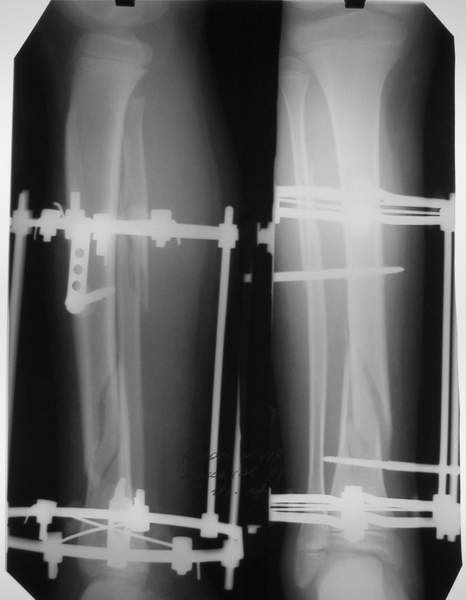

Уважаемый Виталий Евгеньевич,

Помятуя наш недавний разговор о фиксации м.б. кост, высылаю послеоперационные картинки..

Напомню- разбирали случай 17 летнего молодого человека перелом дист тиб.фиб. хирургия после 3 недель с момента травмы( безуспешные попытки закрытой репозиции) Раны заживают первичным натяжением, занимается физиотерапией, пока никаких проблем не наблюдается

Как ты тут оцениваешь восстановление оси большеберцовой кости?

Является ли рутинной практикой у вас использовать снимок противоположной конечности как шаблон для измерения осевых отклонений?

Отправитель: Evgueny Tchekashkine 01 Апрель 2005, 22:45

Согласный я с тобой:-)) есть остаточная вальгусная деформация (по снимку видно перекрывание дист. фрагментом б.б по латеральной поверхности проксимальноо фагмента на 2-3 мм и наружная лодыжка репонирована с укорочением, судя по прямой проекции. Необходимость использования интраоперационно дистрактора была бы оправдана (вручную было непросто *вытянуть* дистальный отломок.)

Отправитель: Vitaly Kazennov 01 Апрель 2005, 22:41

Уважаемый Евгений,

На мой взгляд, Ваша демонстрация неожиданно добавила перцу. Если память мне не изменяет, я говорил об отсутствии показаний к остеосинтезу малоберцовой.

Сейчас можно заикнуться о вредности этой манипуляции с точки зрения риска фиксации в неправильном положении, как это получилось у Вашего пациента. Сначала фиксировали большеберцовую, и надо было на этом остановиться, ин май хамбл опиньон. Потом при закручивании винтов на мощнейшей второй пластине сустав увело на вальгус. С учетом того, что пацану всего 17, я бы удалил пластину с малоберцовой и попытался тем или иным способом устранить смещение, пока не срослось.